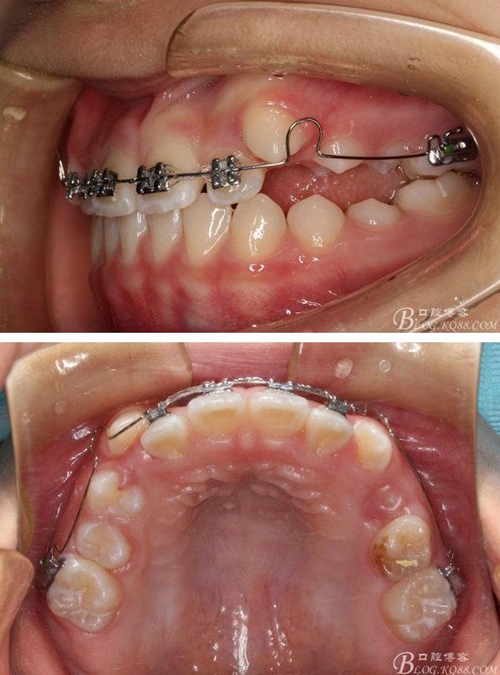

矯治第7個月復(fù)診:磨牙已有咬合接觸。上頜兩個6貼粘貼頰面管,矯治裝置成為真正的“2×4”矯治器。因?yàn)樯项M兩個3唇側(cè)錯位為完全弓外牙,所以在上頜弓絲上彎制了彎曲進(jìn)行避讓。兩個頰面管的近中設(shè)置了“阻擋曲”,目的是使上頜前牙進(jìn)一步唇移,同時為側(cè)方牙齒的萌出創(chuàng)造空間。停止使用固定式低位唇弓Activator。